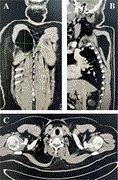

Thoracic endovascular aortic repair (TEVAR) in a combined penetrating thoracic aortic and spinal cord injury

Jacqueline Amm and others

Journal of Surgical Case Reports, Volume 2025, Issue 1, January 2025, rjae771, https://doi.org/10.1093/jscr/rjae771